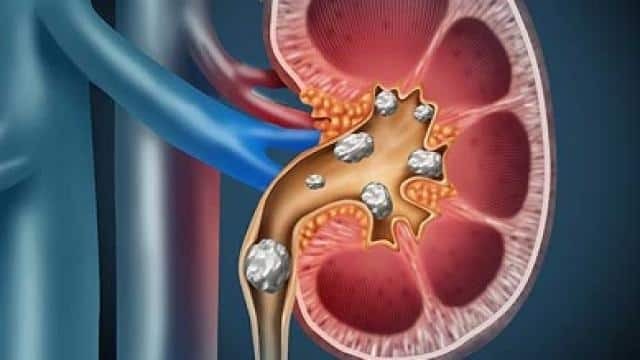

किडनी स्टोन पेशाब में बनने वाले क्रिस्टल से बनने वाला एक कठोर पदार्थ होता है। आमतौर पर पाए जाने वाले किडनी स्टोन में कैल्शियम स्टोन सबसे ज्यादा होते हैं, इसके बाद यूरिक एसिड स्टोन आते हैं।

किडनी की पथरी निकालने के लिए क्या करें? ऐसा माना जाता है कि छोटी पथरी खूब सारा पानी पीने से निकल जाती है। लेकिन अगर कई पथरी हैं या बड़ी हैं, तो आपको खाने-पीने का ज्यादा ध्यान रखना चाहिए। नेशनल किडनी फाउंडेशन (NKF) के अनुसार, आपको किडनी को निकालने के लिए दवाओं के साथ-साथ नीचे बताए उपाय आजमाने चाहिए।